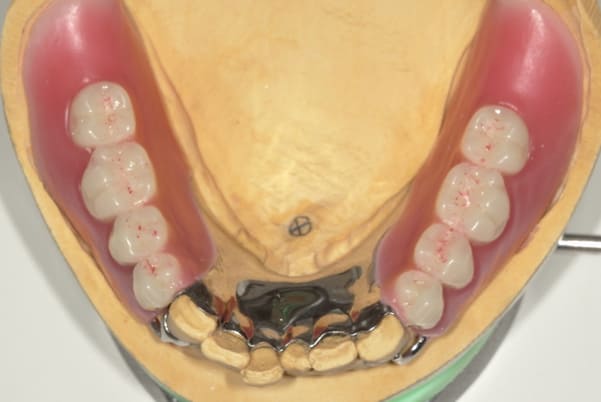

下顎治療前

-

下顎治療後

治療前の入れ歯の奥歯は、治療後の義歯と比較しても分かるように、歯が削れ平らになった状態です。

これにより奥歯のかみ合わせは低くなり、前歯のみが強くあたり、かみ合わせにより上の前歯大きな負担がかかっていたことにより、上の前歯が折れたことが考えられます。

完成前に適合や見た目のチェックでは、咬む力で義歯がたわみ、残りの歯に負担がかからないよう、見えない内側は、金属を用い、強度を増し、また金属のため薄くすることで違和感をなくす設計とし、完成前に試し合わせを行い、装着感、審美性を確認しました。